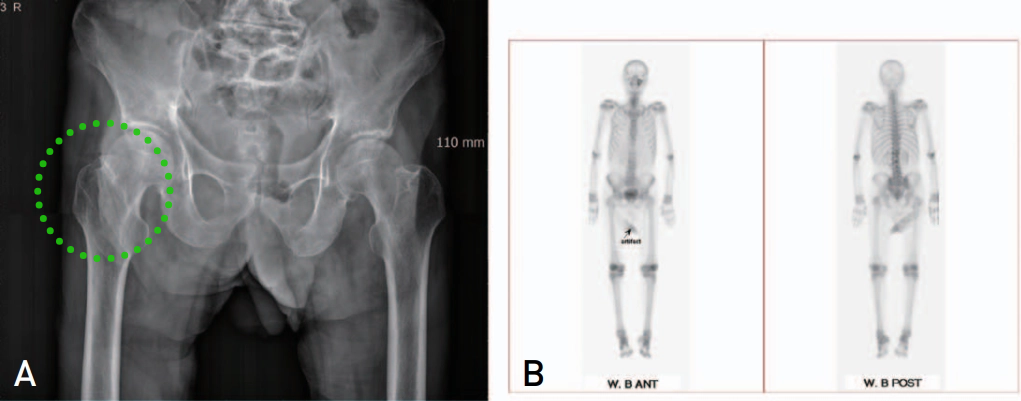

▲图示可见右侧转子间骨折线仅累及外侧1/2骨质,行保守治疗。

结果表明,仅有10%(11/100)在MR检查后证实确实为孤立性大转子骨折,90%均合并不同程度的粗隆间骨折。其中,61例行手术治疗。